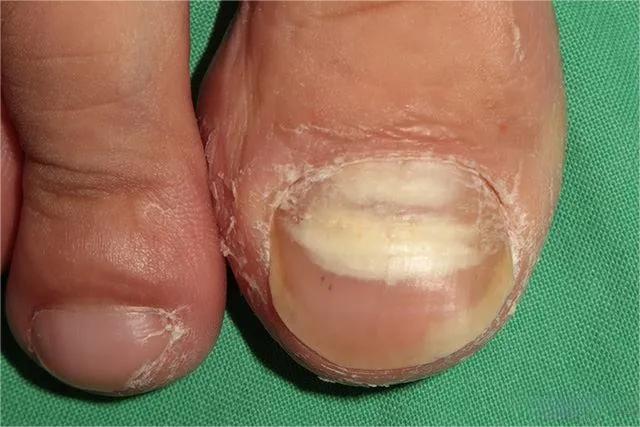

▼由内向外扩散的灰指甲,呈白色。